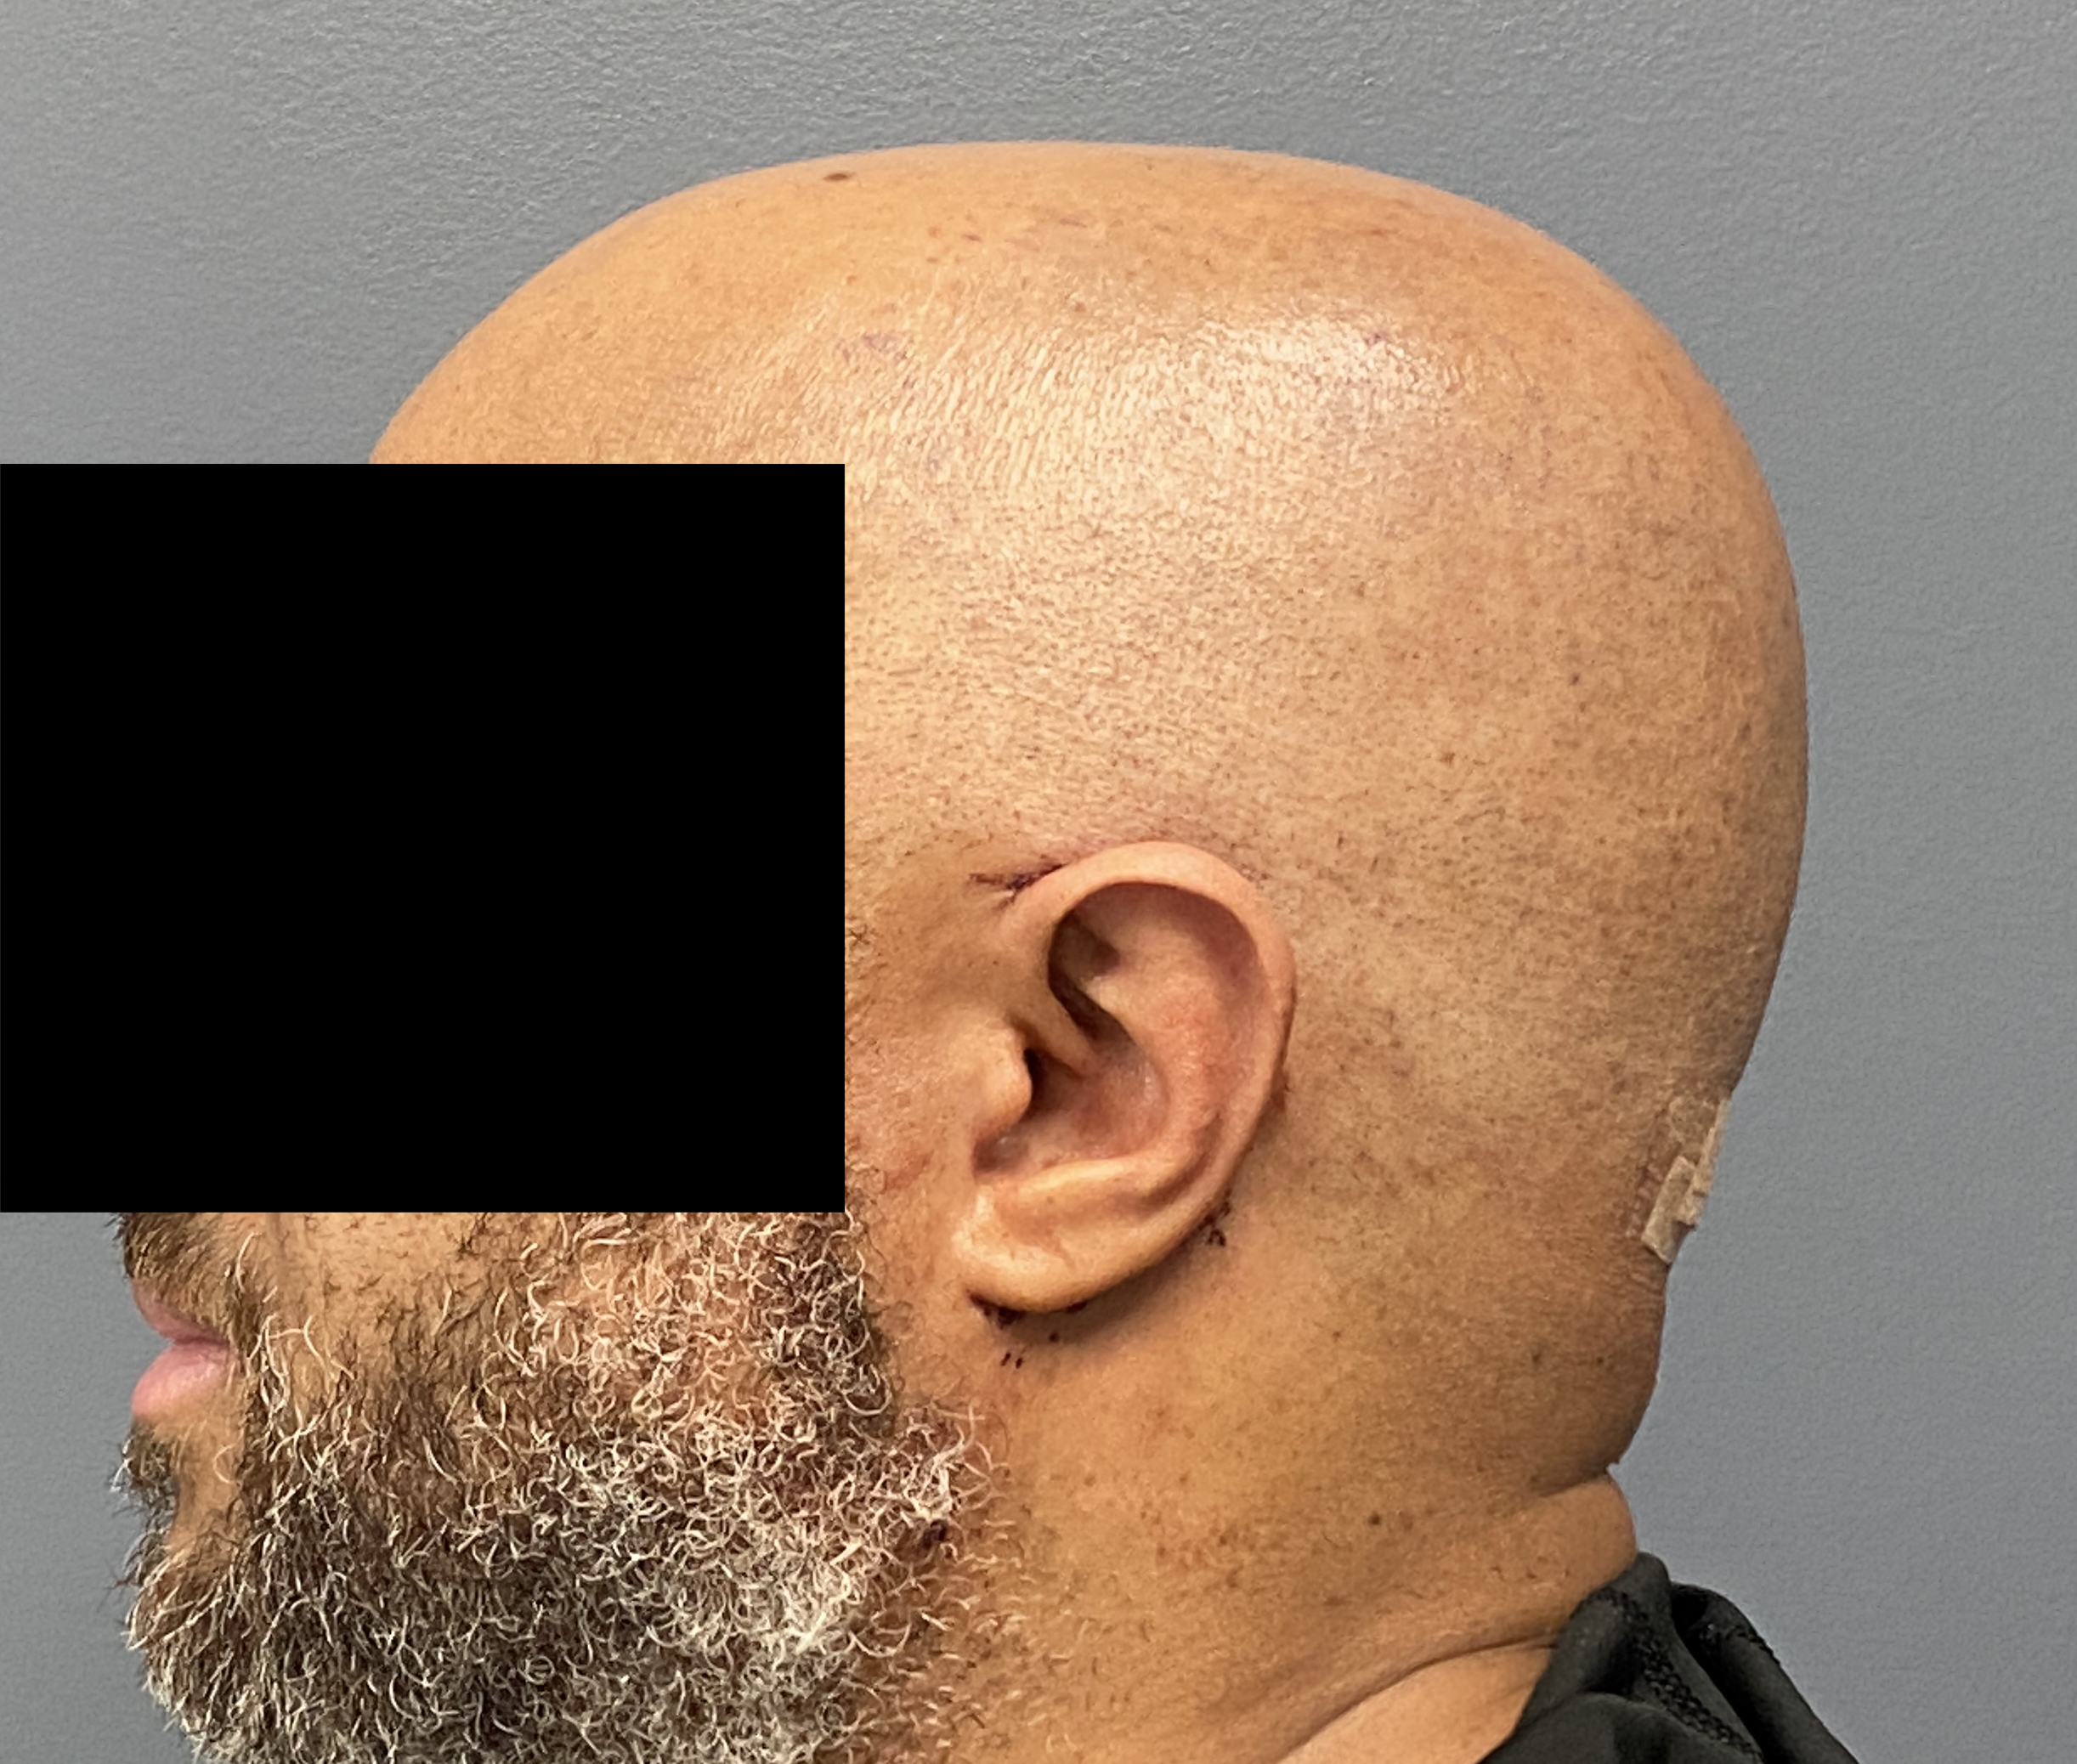

Patient 61

Desire for less wide sides of the head.

Head narrowing surgery performed by removal of posterior temporal muscle through postauricular incisions.

Desire for less wide sides of the head.

Head narrowing surgery performed by removal of posterior temporal muscle through postauricular incisions.